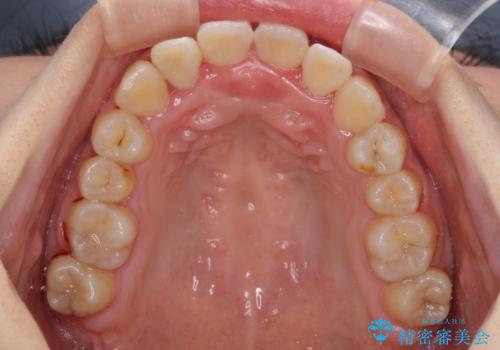

前後に重なった前歯 ワイヤー装置と急速拡大装置を併用したインビザライン矯正

- 前歯の著しい叢生とクロスバイトを気にして来院された患者様です。

叢生が強いため、一見すると抜歯矯正と判断したくなりますが、下顎臼歯が舌側に倒れていることから、上顎骨を側方拡大し、非抜歯矯正の可能性を検討することとしました。

急速拡大装置による上顎骨の側方拡大が思った以上にうまくいき、非抜歯での矯正が可能となりました。

内側に倒れていた下顎の臼歯は起き上がり、清掃性も大幅に改善されました。